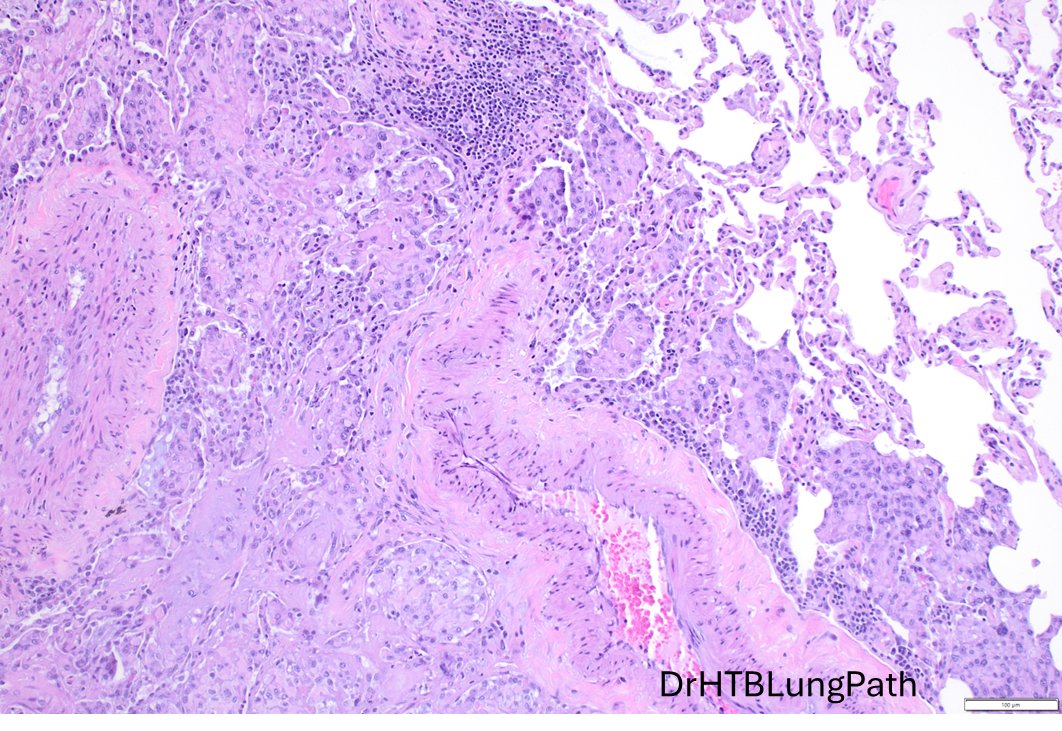

Just out in AJSP – a paper from our group describing a MAJOR new oddity. Tumors that normally arise in the jaw from tooth🦷precursors (ameloblastoma) – but as lung primaries 🫁! This was a neat collaboration b/w MSKCC, Mayo and UTSW where these cases were encountered independently, and we put our heads together with the help of original contributors and fellows to tackle this puzzle. Time will tell if these are truly exceptional or have been underrecognized. journals.lww.com/ajsp/fulltext/… @JLHornick @ENTpathology @MSKPathology @PulmPathSoc @yro854 @thoracicpath @Path_Matt @SansanoValero @AndreMo77438628